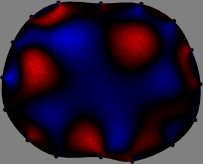

To explain the FER method, we closely examine the correlations among column vectors of the sensitivity matrix , described in Fig. 2. The correlation between and can be expressed as

for [23]. This shows that the column vector is like an EEG (electroencephalography) data induced by dipole sources with directions at locations . Given that two dipole sources at distant locations produce mutually independent data, the correlation between and decreases with the distance between and . Fig. 2 shows a few images of the correlation as a function of for four different positions . The correlation decreases rapidly as the distance increases. In the green regions where the correlation is almost zero, is nearly orthogonal to .

Fig. 2 shows that if and are far from each other, the corresponding columns of the sensitivity matrix are nearly orthogonal. This somewhat orthogonal structure of the sensitivity matrix motivates an algebraic formula that directly computes the local ensemble average of conductivity changes at each point using the inner product between changes in the data and a scaled sensitivity vector at that point: